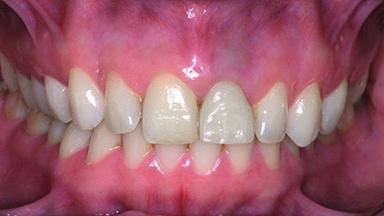

A 28-year-old patient presented at her general dentist’s office and complained about the appearance of her tooth 21. The patient had a history of trauma to this tooth. Endodontic treatment had been performed in the past and a crown placed on the tooth. A procedure to replace the old crown was performed by her dentist; however, a perforation on the middle third of the root occurred, and extraction of tooth 21 was suggested. Upon clinical and radiographic examination of the patient, who had been referred to us, replacement of tooth 21 by a dental implant appeared to be indicated.